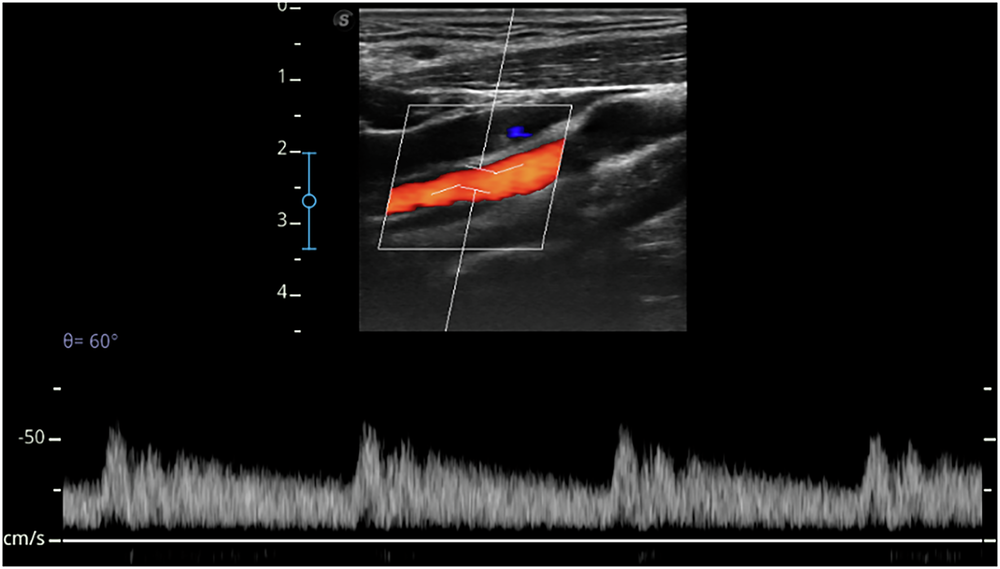

Fig. 6: Hemodynamic features of the ICA in a 21-year-old male participant.

Hemodynamic features of the ICA from a left ICA ultrasound Doppler image of the participant. ICA internal carotid artery.